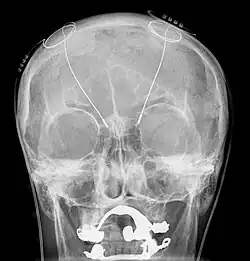

The leads are two coiled wires insulated in polyurethane with four platinum-iridium electrodes that allow delivery of electric charge from the battery pack implanted in the chest wall. The battery is usually situated subcutaneously below the clavicle and rarely in the abdomen. The leads, in turn, are connected to the battery by an insulated extension wire which travels from the chest wall superiorly along the back of the neck below the skin, behind the ear, and finally enters the skull through a surgically made burr hole to terminate in the deep nuclei of the brain.[20] Microelectrodes (usually 1–5) are delivered through the burr holes. A combination of microelectrode recordings, microstimulation, macrostimulation, and neurophysiological mapping at the level of single neurons or local neuronal populations through local field potential analyses are used to increase specificity of placement for the most precise neurophysiologic effect possible.[2]

DBS leads are placed in the brain according to the specific symptoms to be addresses and implantation may take place under local or general anesthesia. A hole about 14 mm in diameter is drilled in the skull and the probe electrode is inserted stereotactically, using either frame-based or frameless stereotaxis.[22] During the awake procedure with local anesthesia, feedback from the individual is used to determine the optimal placement of the permanent electrode. During the asleep procedure, intraoperative MRI is used to image the brain during device placement.[23] The installation of the IPG and extension leads occurs under general anesthesia.[24]